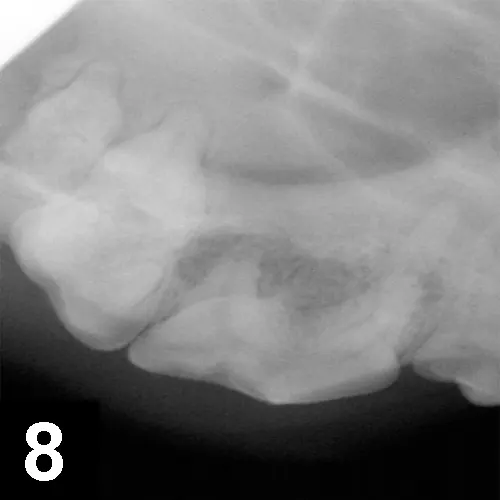

A maxillary extraoral draining tract rostral to the eye is most commonly associated with chronic infection (periodontal or endodontic) of a maxillary premolar or molar tooth (Figure 6). In brachycephalic breeds, it might even be the canine tooth. Dental disease is subgingival, and both periodontal and endodontic infections can result in maxillary draining tracts. There may be associated bone proliferation or reaction, and the region may be firm on palpation. Dental disease should be the top differential for these lesions before dermatologic conditions, ophthalmologic conditions, or tumors are considered. The infected tooth can be identified with general anesthesia, oral examination, periodontal probing, and intraoral radiographs of the maxillary regional dentition on the ipsilateral side of the draining tract (Figures 7 and 8) with similar radiographs of the contralateral side for comparison. Surgical extraction of the infected tooth or teeth is often necessary. The carnassial tooth is not always at fault; therefore, intraoral radiographs are needed to diagnose the infected tooth, which could be any of the ipsilateral dentition (eg, first maxillary molar).